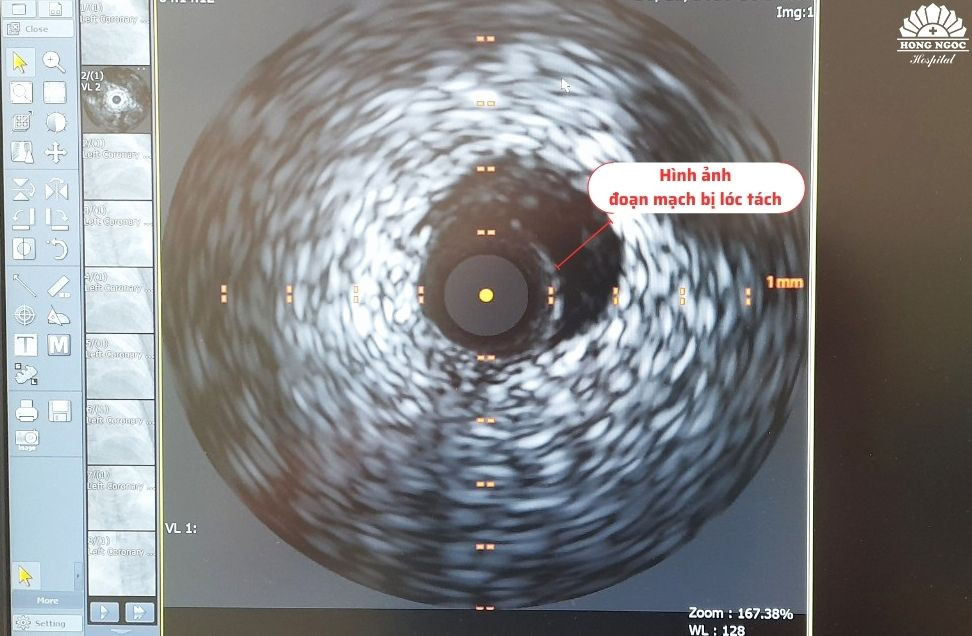

Đáng chú ý, trước đó sức khỏe bệnh nhân hoàn toàn bình thường, không có tiền sử bệnh tim mạch nhưng khi nhập viện, các triệu chứng lâm sàng lại hết sức nghiêm trọng, men tim tăng cao, ở mức 2816ng/L nên được chỉ định chụp mạch vành kết hợp siêu âm trong lòng mạch IVUS. Kết quả chụp cho thấy bệnh nhân bị nhồi máu cơ tim cấp do lóc tách đoạn 2 - 3 động mạch liên thất trước.

ThS.BS Nguyễn Đình Công, bác sĩ trung tâm Can thiệp tim mạch Hồng Ngọc, là người trực tiếp can thiệp cho bệnh nhân Hà chia sẻ: “Hầu hết các trường hợp bị nhồi máu cơ tim cấp đều do huyết khối hoặc các mảng xơ vữa gây hẹp mạch vành… Tuy nhiên, với những trường hợp không có tiền sử bệnh như bệnh nhân Hà, kèm theo các triệu chứng lâm sàng nghiêm trọng thì việc sử dụng kỹ thuật siêu âm trong lòng mạch là vô cùng cần thiết. Kỹ thuật này giúp chẩn đoán chính xác bệnh nhân bị hẹp hay lóc tách động mạch vành. Nếu chỉ chụp mạch vành số hóa xóa nền, hình ảnh hiển thị lòng thật và lòng giả rất khó phân biệt nên cần phải sử dụng IVUS vì kỹ thuật này thể hiện rõ được ba lớp cấu trúc của thành động mạch vành.”

![]() |

| Hình ảnh siêu âm trong lòng mạch IVUS trước can thiệp của bệnh nhân |